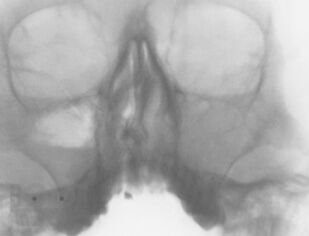

Представлены данные об этиологии, патогенезе, классификации форм хронического синусита. Приведен обзор современных методов диагностики и лечения. Обсуждается консервативное лечение синуситов с учетом особенностей микрофлоры, освещены не только стандартные хирургические подходы, но и некоторые базовые и прикладные вопросы функциональной эндоскопической риносинусохирургии.